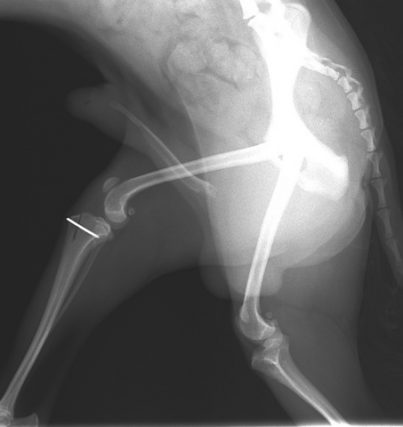

レントゲン検査

左右後肢の膝蓋骨の内方脱臼を確認しました。

左右共に内側に脱臼した膝蓋骨

整復後の膝蓋骨(向かって右)

術後レントゲン写真